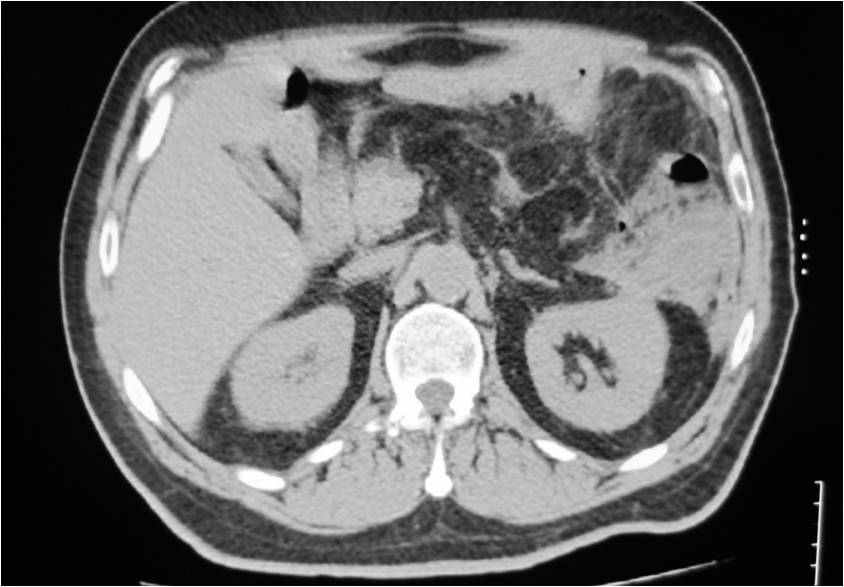

- Large abdominal abscess post- pancreatic surgery

- Successful drainage